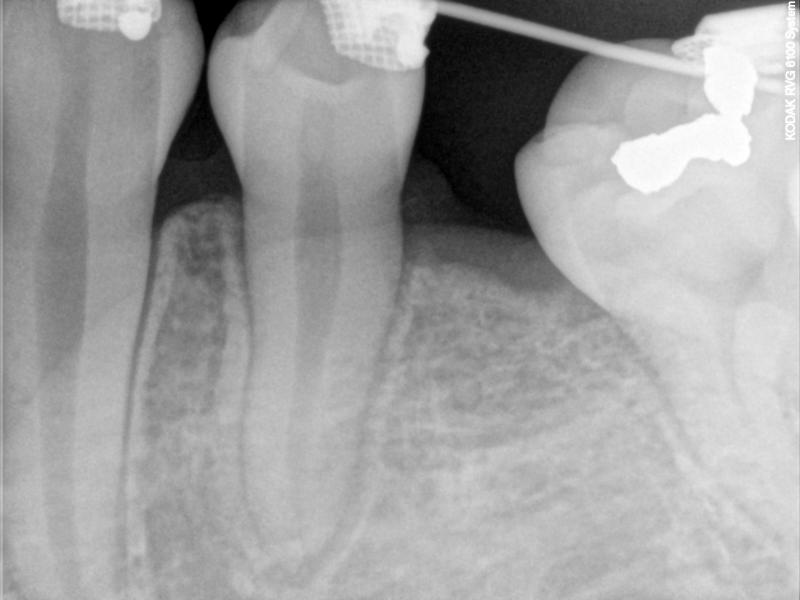

Fig. 3. PA taken for TAD location (after LLE extracted)

© Copyright 2007-2014, Vu Orthodontics. All rights reserved.